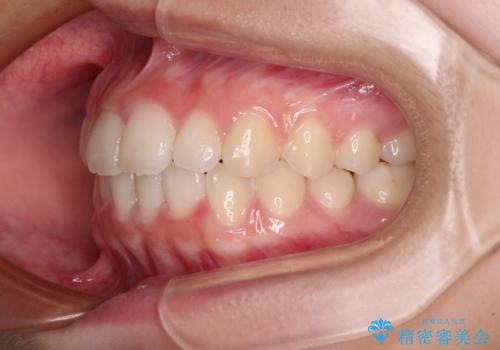

上下ともに少し捻れが残っていたため、治療の継続を提案しましたが、本人も親御さんも満足とのことで、治療を終えました。

捻れの改善により突出感も改善されました。